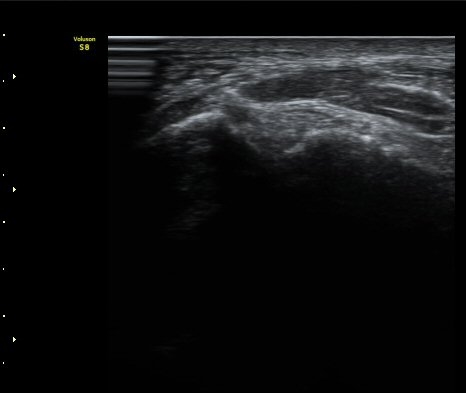

ÃÊÀ½ÆÄÅõ½ÃÇÏ ºÎÇϰ˻翡¼­ ºñ°ñ°ú ÀÎ´ë ºÎÂøºÎ¿Í ºñ°ñ°ú °Å°ñ »çÀ̰¡ ¹ú¾îÁø´Ù

(樨毢 1)

Àü°Å°ñºñ°ñÀÎ´ë ¼Õ»óÀÌ °üÂûµÇ´Â °æ¿ì ¹Ýµå½Ã ÃÊÀ½ÆÄÅõ½ÃÇÏ ºÎÇϰ˻縦 ½ÃÇàÇÏ¿©

ÀδëÀÇ ¿ÏÀü ÆÄ¿­·Î ºÒ¾ÈÁ¤¼ºÀ» º¸ÀÌ´Â °æ¿ì 3ÁÖ ÀÌ»ó ¼®°í°íÁ¤ÀÌ ¹Ù¶÷Á÷ÇÏ´Ù.